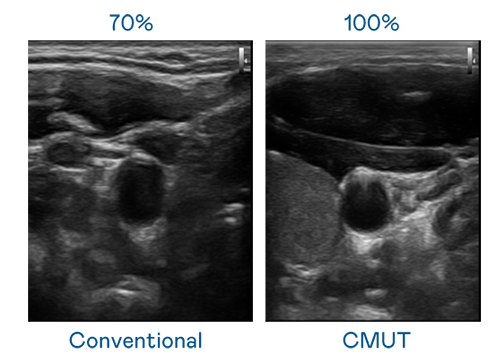

CMUT 技术是一种用电容式微机电元件来产生超音波讯号的技术。与传统 PZT 压电式技术相比,CMUT 频宽增加 30%,更宽频的超音波讯号让影像解析度大幅提升,是实现高影像品质医疗超音波扫描、促进精准医疗发展的关键技术。

大频宽带来超清晰影像

超音波影像的解析度高低,首先取决于探头能发出的讯号频宽。豪运国际 CMUT 可提供高清晰的超音波讯号,提供高频宽、高灵敏度、影像纹理细节更高的超音波影像,协助医护人员缩短影像判读时间及利用精准的医疗影像进行诊断。